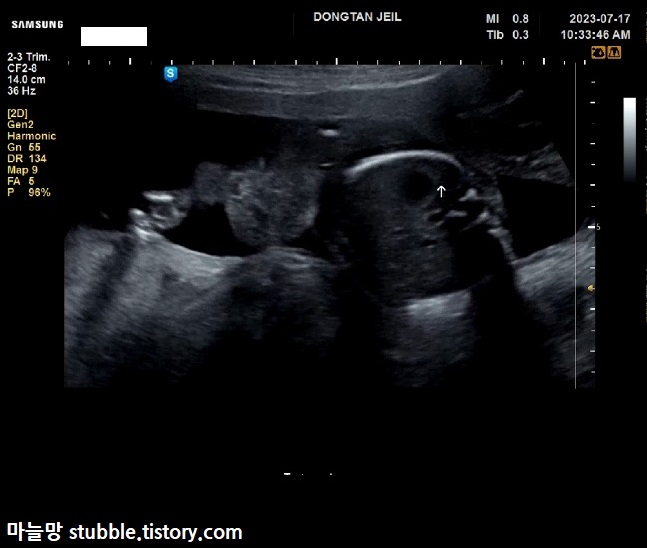

질초음파로 자궁 경부 길이를 잽니다.

19주 4일차에 4.02cm로 안정권 입니다.